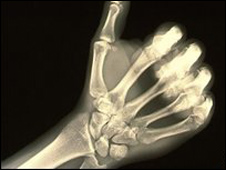

الأشعة السينية أعظم إختراع علمي عبر العصور

تفوقت آلة الأشعة السينية (أشعة إكس) في اقتراع شعبي أجراه متحف العلوم في لندن على 10 اكتشافات علمية، منها سفينة الفضاء "أبولو 10" والبنسلين وقاطرة ستيفينسون البخارية (صاروخ ستيفينسون) والشريط الوراثي (شريط الـ DNA)، لتُعتبر بذلك "أعظم الاختراعات عبر العصور".

يُذكر ان أشعة إكس مكَّنت الإنسان للمرة الأولى من رؤية داخل جسم الإنسان دون الحاجة لإجراء أي عمل جراحي وشق الجسم، مما اعتُبر تقدما علميا هائلا.